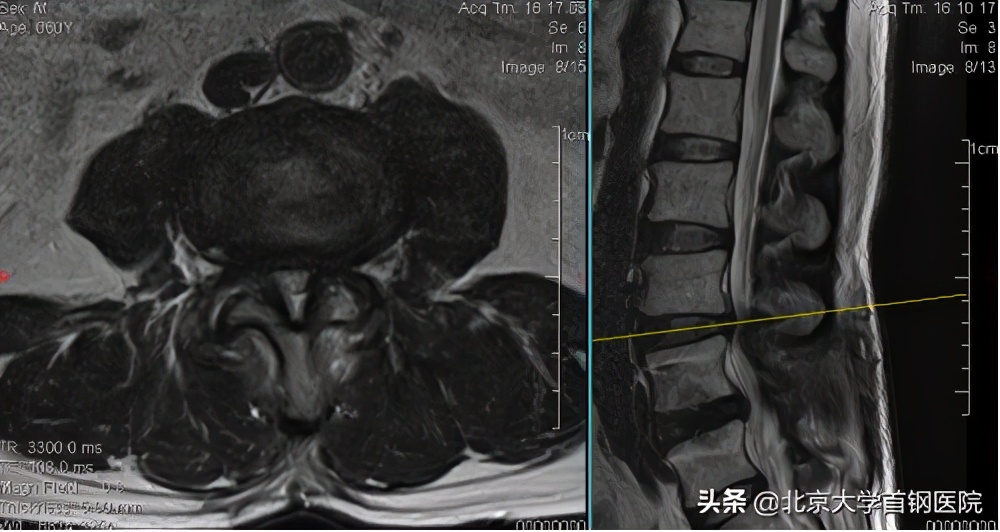

60岁的孙大爷,因剧烈腰痛,同时伴双下肢疼痛麻木、间歇性跛行,严重影响生活质量,2月前在当地医院诊断为“腰椎管狭窄症”并行腰椎手术治疗,但效果欠佳,后慕名找到我院骨科副主任、脊柱组组长刘正教授就诊。在完善MRI检查后,刘正教授发现患者腰4-5椎管狭窄已经减压固定,但腰3-4节段双侧关节突关节增生内聚,黄韧带肥厚,侧隐窝及中央椎管明显狭窄,硬膜囊和神经明显受压。

经过询问病史、查体和阅片后,刘正教授认为患者虽然已经行腰椎减压固定手术,但邻近节段显示严重椎管狭窄,采用微创手术治疗效果更佳,特别是单侧双通道脊柱内镜技术对于减压内固定邻近节段的腰椎管狭窄有明显的技术优势,通过单侧入路,解决双侧问题,且不需要翻修原有的固定物或增加螺钉固定,手术伤口不到2cm,创伤小、神经减压彻底、恢复快。